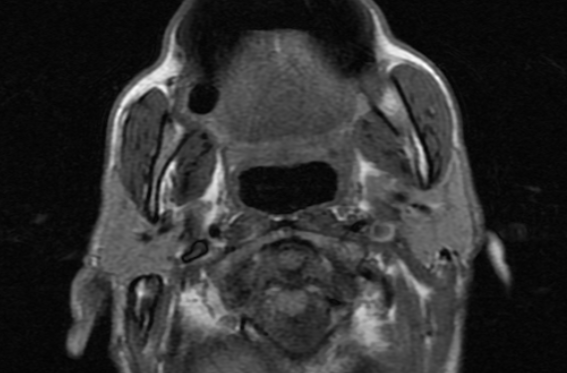

CTA MRI Brain

MRI Brain X-Ray